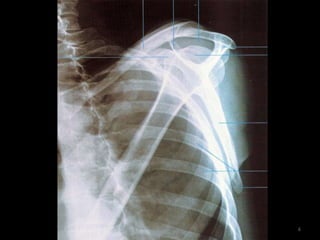

Incidência AP da Escápula2

3